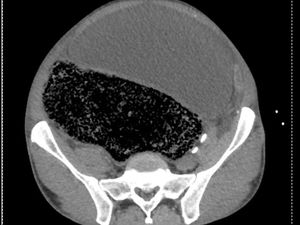

Pria 57 tahun mengeluh mendadak tak bisa berjalan. Setelah menjalani pemeriksaan, dokter menemukan 2 liter feses berada dalam perutnya. Bagaimana bisa?